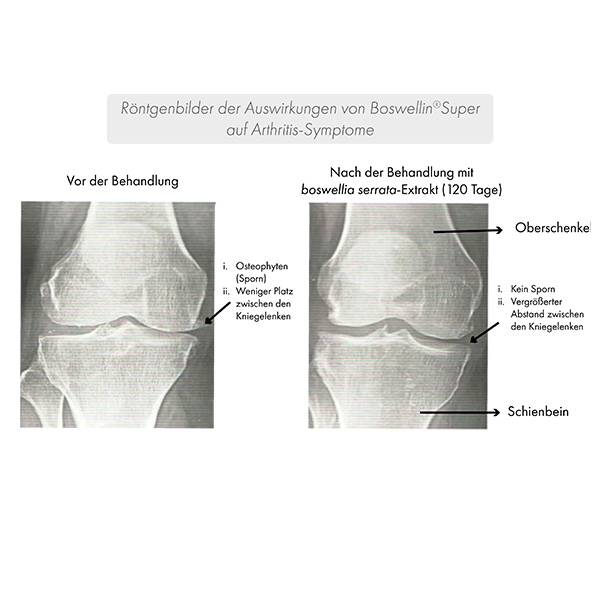

Parallel dazu wurde die Verbesserung der Symptome über Röntgenbilder nachgewiesen.

Nach 120 Tagen wurde eine Verbesserung des Gelenkspalts sowie eine Abnahme der Osteozyten gezeigt.